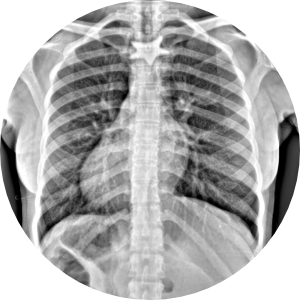

Humanos

- Niños

- Adultos

- Pacientes geriatras

- Seguimiento post cirugía ortopédica

Llame, nosotros vamos a su domicilio.

(ZONA SUR DE LA CD DE MÉXICO)

Ideal para pacientes con incapacidad para trasladarse al hospital o moverse. Fracturados, con fijación externa, osteoporosis, niños, adultos, pacientes geriatras, seguimiento post cirugía ortopédica.

SI NO QUIERES IR AL HOSPITAL, AGENDA UNA CITA NOSOTROS VAMOS